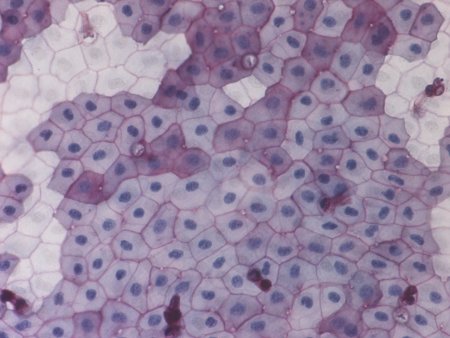

Гепатоциты микрофотография